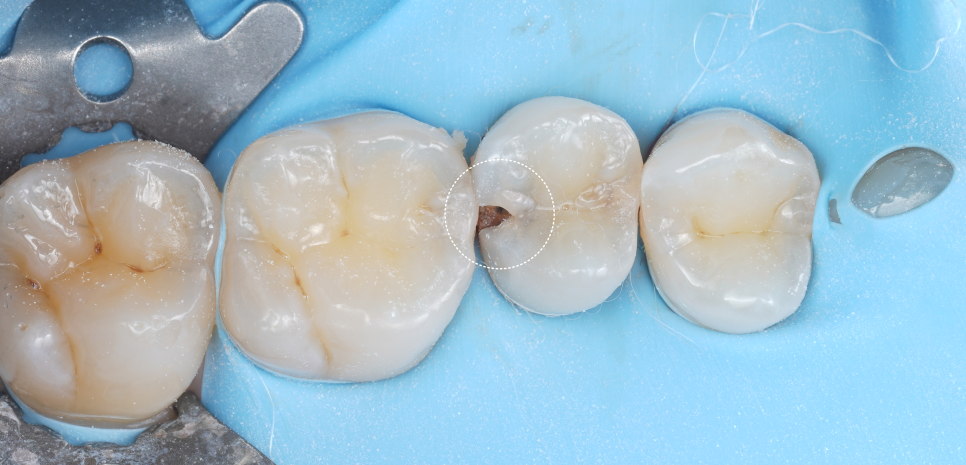

촬영일 : 251013

마취 없이도 충분히 진행해도 될 정도였고, 충치를 깨끗이 제거했어요.

이때, 러버댐으로 침과 습기를 완전히 차단해 재료가 제대로 붙을 수 있는 환경을 만들어줬어요. 그다음 신경 노출 부위에 MTA를 도포하여 신경을 안정시켰어요.

이 재료는 신경을 감싸며 염증을 막고 치아가 스스로 회복할 수 있게 도와준답니다. 쉽게 말해 치아 속에 자연 치유의 방패를 세워주는 셈이에요^^ (다음에 좀 더 자세히 설명드릴게요!)

마지막으로 레진을 여러 겹 쌓아 올리며 형태를 복원했는데요. 씹는 힘의 방향, 인접 치아와의 접촉점, 미세한 높낮이까지 모두 고려하면서 자연스러운 형태로 완성했어요.